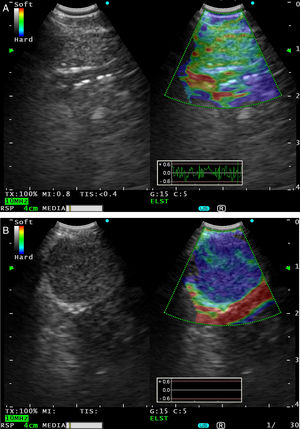

Observación clínicaCaso 1Varón de 66años, exfumador desde hacía 4 años, con antecedentes de EPOC moderada y derrame pleural izquierdo en estudio con citología negativa para malignidad. En los últimos 4meses había presentado 2 episodios de neumonía en el lóbulo inferior izquierdo (LII). Consulta en urgencias por dolor pleurítico izquierdo, incremento de la tos y mal estado general. La PET-TAC mostró una masa necrótica hipermetabólica en LII y adenopatías hipermetabólicas paratraqueales inferiores izquierdas, subcarinales-paraesofágicas izquierdas y paraaórtica izquierda, compatibles con metástasis. Se practicó una broncoscopia, en la que se apreció una tumoración endobronquial en el bronquio del segmento 10 de LII. La citología del cepillado bronquial fue compatible con carcinoma escamoso. Se efectuó una ecobroncoscopia (BF-UC180F Olympus, Japón), en la que se puncionaron ganglios 4R n.°1 (5,4mm), 4R n.°2 (5,9mm), 4R n.°3 (7,5mm), 7 n.°1 (6,6×21,4mm), 4L n.°1 (13,1×15,4mm) y 7 n.°2 (12,6×15,5mm) tras cambio de aguja. Los ganglios 7 n.°1 y 7 n.°2 se examinaron en el modo elastografía (procesador EU-ME2 Premier Plus Olympus, Japón), obteniéndose un patrón cualitativo de imágenes en color donde las áreas de tejido de mayor consistencia estaban en azul oscuro, las intermedias en verde y las más blandas en rojo (fig. 1A y B). En el modo de pantalla doble, la imagen del modoB se muestra a la izquierda, y a la derecha se superpone la imagen de la codificación de colores de las respuestas de tensión con la imagen ultrasonográfica del modoB. La región de interés para los cálculos de la elastografía se seleccionó manualmente e incluyó el ganglio y los tejidos adyacentes. Las punciones fueron negativas para células malignas, excepto las de 4L n.°1 y 7 n.°2, con diagnóstico de metástasis de carcinoma escamoso y necrosis tumoral.

A) La imagen de USEB convencional en modoB de escala de grises (izquierda) y en modo elastografía en tiempo real mediante USEB (derecha) muestra un ganglio linfático subcarinal benigno de 6,6mm, visualizado como un área de rigidez intermedia (verde). B)La imagen de elastografía por USEB (derecha) muestra una adenopatía subcarinal maligna de 12,6mm que se visualiza como un área dura (azul oscuro-cian) debida a infiltración ganglionar por carcinoma escamoso.